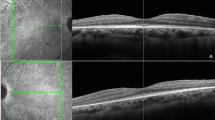

Structural OCT analysis

Structural OCT images were acquired by means of a spectral-domain OCT instrument (Spectralis HRA2 + OCT, Heidelberg Engineering; Heidelberg, Germany). We included only high-quality images (ART > 25) and used the segmentation tool included in Heidelberg HEYEX device to measure the thickness of all retinal layers automatically on an ETDRS-9 sectors grid (central, inner nasal, inner superior, inner temporal, inner inferior, outer nasal, outer superior, outer temporal, and outer inferior). The tool was used under the supervision of two expert ophthalmologists (AA, EA), producing an ETDRS thickness map for the following layers: central macular thickness (CMT), retinal thickness (RT), retinal nerve fibre layer (RNFL), ganglion cell layer (GCL), inner plexiform layer (IPL), inner nuclear layer (INL), outer plexiform layer (OPL), outer nuclear layer (ONL), and ellipsoid zone thickness (EZ). In addition, the same graders performed the measures of choroidal thickness (CT), Haller layer thickness (HLT) and Sattler layer thickness (SLT). CT and HLT were obtained from a horizontal structural OCT scan centred on the fovea, calculating the mean value of five samples (subfoveal, 750 µm and 1500 µm nasal and temporal). SLT value corresponded to the result of (CT-HLT).

ETDRS-based quantitative analysis

The complete ETDRS analysis is shown in Supplementary Table 1, while the merged thickness analysis of inner and outer grids is shown in Table 3. Looking at the global values, RNFL, GCL, IPL, ONL and EZ were found to be significantly thinner in RP than in controls (p < 0.05), whereas INL and OPL were significantly thicker in RP eyes (p < 0.05). At the same time, FAF intensity and MP retinal sensitivity were significantly lower in RP than in control eyes (p < 0.05). A separate analysis of the inner rings confirmed these findings (all p < 0.05), the only exception being RNFL, which largely matched healthy values (p > 0.05). In contrast, looking at the outer ring values, we find that all the global findings were confirmed (all p < 0.05) except for INL values, which proved analogous to those of healthy controls (p > 0.05). We detected no significant changes in all the parameters after one year of follow-up (all p > 0.05). The distribution of retinal layer thickness changes occurring in RP is plotted in Fig. 1. The detailed description for each layer is provided in the figure legend. Overall, all ETDRS sectors displayed considerable changes in retinal thickness and MP retinal sensitivity values; it is worth noting the evident alterations detected in sector S1 with regard to IPL thinning, INL and OPL thickening, and MP values (Fig. 1). RP eyes exhibited diffuse reductions in the FAF intensity pattern affecting both inner and outer sectors. Remarkably, an evident FAF intensity reduction was detected in the central sector (Fig. 1 and Supplementary Table 1).

For each plot, healthy controls are shown in blue, RP values at baseline are shown in orange and RP values at 1-year follow-up are shown in grey. In RNFL the most extensive thinning occurs in S2, N2 and I2. Conversely, GCL is distinguished by diffuse thinning involving all the ETDRS grid sectors, the most pronounced being S1, S2, I1 and I2, with C being the only exception. IPL shows a diffuse thinning in S1, N1, I1, T1 and T2, whereas it is found to be thicker in C. Conversely, INL proves thicker overall in C, S1, N1, I1, T1, I2 and T2, whereas OPL turns out to be thicker in C, S1, S2, N2, I2 and T2. In both INL and OPL, the most pronounced changes are detected in S1. ONL and EZ prove to be thin throughout in RP. As regards MP retinal sensitivity, the lowest values are detected in the outer ring sectors. Interestingly, the most extensively affected inner sector is S1, while the others share similar MP values. Lastly, FAF displays reduced diffuse intensity, affecting both inner and outer sectors, and this reduction is curiously particularly marked in the C sector.